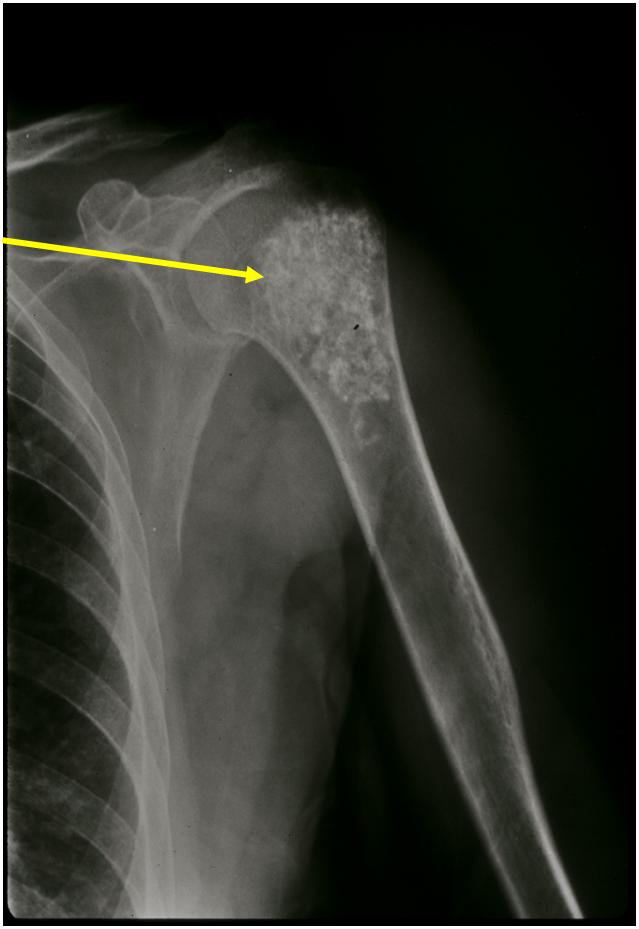

- Localized, radiolucent defect usually with punctate calcifications

- Calcifications are typical but not always present

- Matrix may demonstrate various degrees of calcification

- Calcifications are stippled, punctate, popcorn like calcifications and “Ring and Arc” calcifications

Plain X-Ray:

- Geographic lytic lesion

- Central often metaphyseal in long bones

- Can be eccentric also

- Expansile remodeling with thinned cortex

- Chondroid matrix with calcifications in majority of tumors

- Approximately 20% have limited or no calcifications

Ring and Arc Calcifications Minimal Endosteal Scalloping Cortex Intact No Soft Tissue Component No Periosteal Reaction

Ring and Arc Calcification No Endosteal Scalloping

Metaphyseal Tumor Heavy Calcifications Ring and Arc Pattern of Calcifications Minimal Endosteal Scalloping No Cortical Destruction No Periosteal Reaction No Cortical Destruction No Soft Tissue Component

Geographic Lesion Bony Expansion Minimal Calcification Some Enchondromas do not calcify